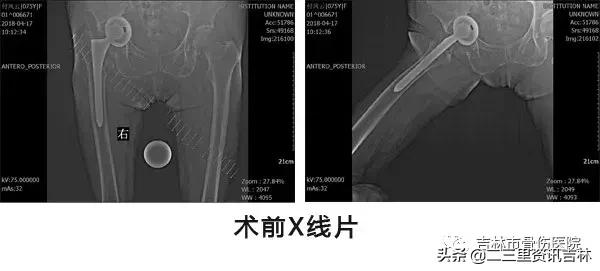

该患于2008年6月因“右股骨颈骨折”在外院行“右侧髋关节置换术”,术后恢复良好,休养至今,于2016年11月30日在自家走路时不慎滑倒摔伤,伤后出现右髋部肿痛,不敢活动,未经处置,在家休养至今未见缓解,现为求系统治疗前来我院就诊,经门诊医生查体拍片后以:“右侧髋关节置换术后假体周围骨折”收入院。

患者入院后给予常规检查,经三级医师查房,临床诊断确诊,查无明显手术禁忌症后在腰硬+全麻麻醉下行“右侧髋关节置换术后假体周围骨折关节翻修术”,术后抗感染、消肿、抗凝、关节功能松动练习等对症治疗,术后患者恢复良好。